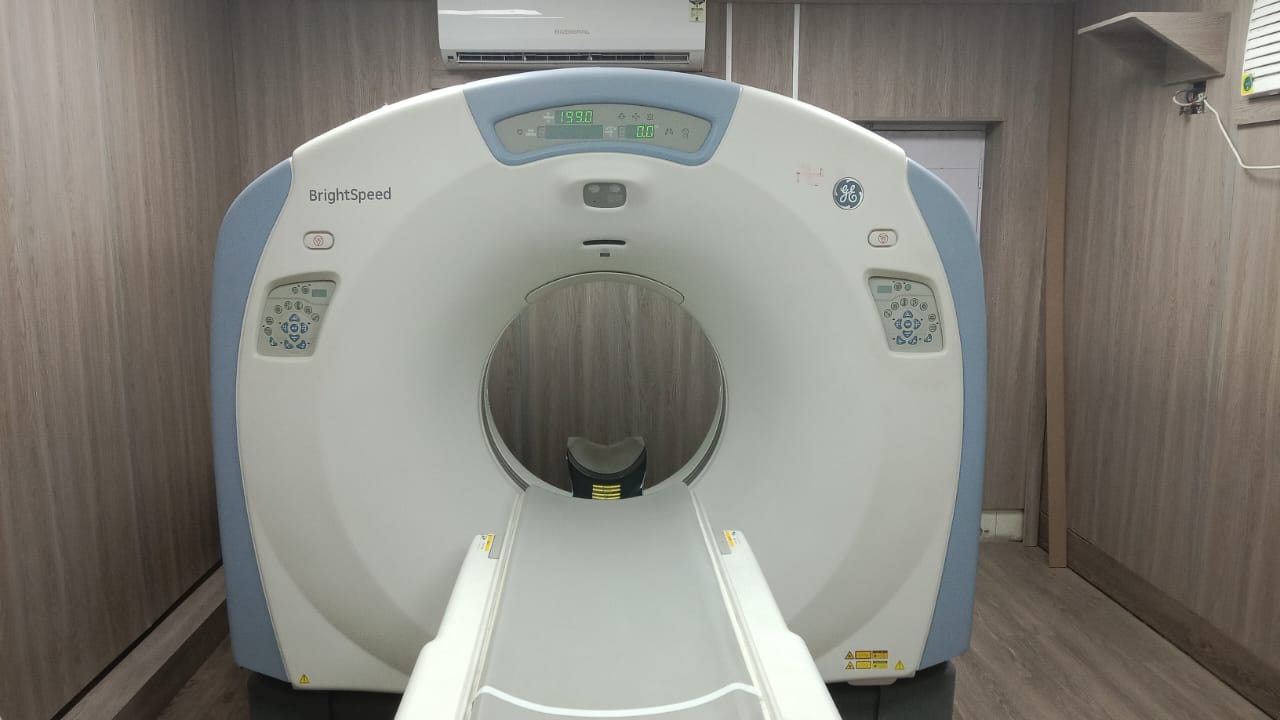

C.T. SCAN

Multislice CT Scan machine of Wipro GE brightspeed